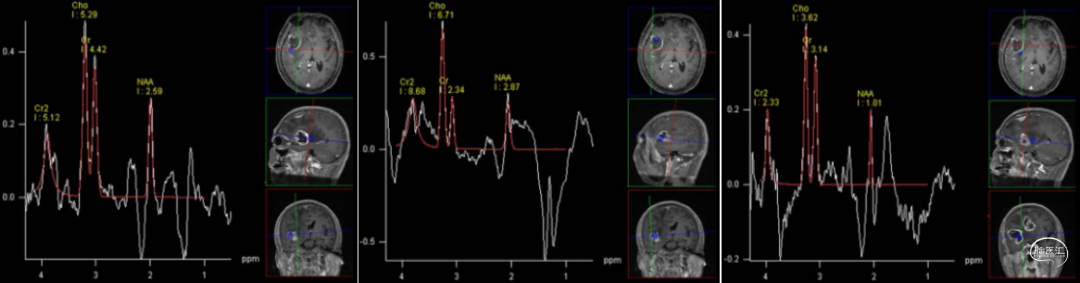

2020-02-12 MRI:双额叶大脑镰旁、胼胝体,右侧颞叶见两个不规则团片状异常信号影,病灶局部形成囊实性肿块,大小分别约3.9×4.6cm及4.0×3.2cm,实性部分T1WI呈等信号,T2WI呈稍高信号,FLAIR呈高信号,高b值DWI呈稍高信号,相应ADC呈低信号,边缘见少许斑点状及条索状T1WI高信号影,增强扫描呈不规则环形强化,病灶周围见大片状水肿,右侧侧脑室前角、体部、后角明显受压,中线结构左偏,脑干受压稍向左偏移。DTI序列图像质量欠佳,示病灶实质区FA值明显降低,纤维束中断破坏,水肿区FA值降低,累及胼胝体及右侧内囊纤维。MRS示病灶实质区Cho升高,NAA降低,Cho/NAA明显升高。另见右额凸面一明显均匀强化病灶,宽基底位于凸面硬膜,边界较清,大小约2.3×2.0cm,T1WI呈低信号,T2WI呈稍高信号,FLAIR呈高信号,高b值DWI呈高信号,相应ADC呈等信号,增强扫描明显均匀强化,邻近脑膜增厚强化呈“脑膜尾征”,病灶邻近颅骨骨质增生。检查印象:临床提示颅内占位,颅脑MRI平扫+增强+DWI+DTI+MRS+MRS:双侧额叶大脑镰旁、胼胝体,右侧颞叶占位,考虑脑肿瘤所致,结合MRS,倾向恶性肿瘤,胶质瘤?不除外高级别脑膜来源肿瘤,脑中线结构左偏,脑干受压稍向左偏移。另,右侧额部肿块,考虑脑膜瘤可能性大